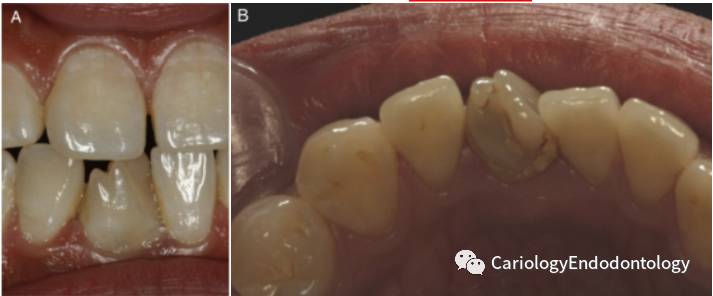

2)口内检查发现右下中切牙冠部解剖异常。见图1 AB

2)在牙齿内部,存在一个从髓腔延伸到根尖孔部位的内陷。本病例的牙内陷为型牙内陷。见图1C